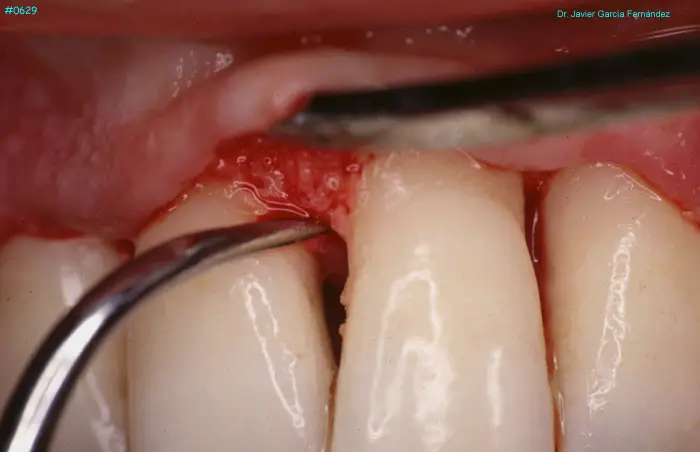

Atlas of Surgical Techniques in Periodontics. Chapter III. Atlas de Técnicas Quirúrgicas en Periodoncia